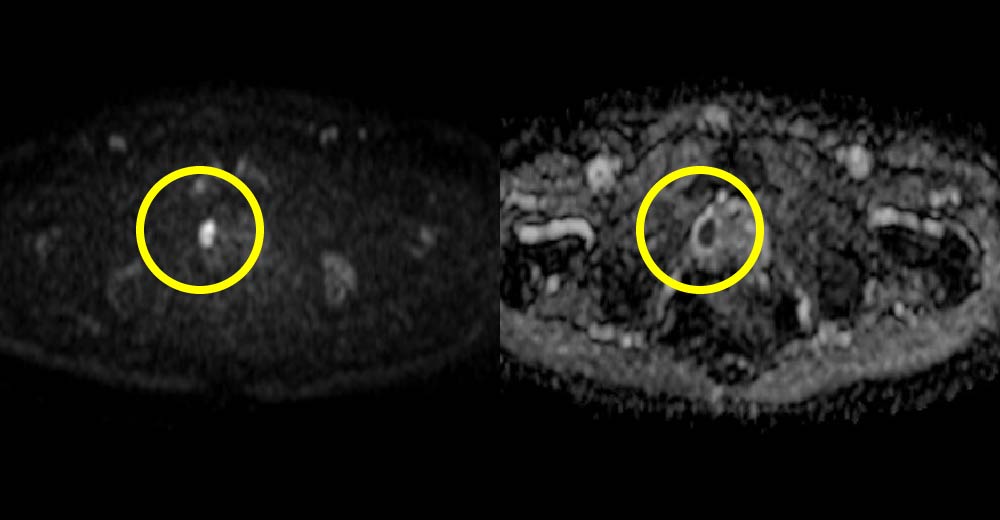

前立腺がん症例です。前立腺生検前にMRI撮影を行っています。

左:MRI Diffusion 右:MRI ADC map